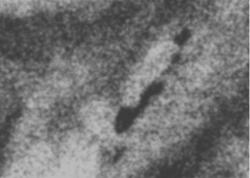

Протокол рентгенологического исследования (кратко). На снимке в прямой проекции (1) общая скиалогическая картина инволютивной молочной железы, с хорошо прослеживающимися на фоне жировой ткани соединительнотканными компонентами стромы, отдельными очаговыми уплотнениями паренхимы железы. В верхнем наружном квадранте прослеживается цепочка макрокальцинатов различной величины и формы, по расположению, напоминающая ход млечного протока, что хорошо видно также на снимке в боковой проекции (2). В верхнем внутреннем квадранте железы, а также ретроареолярно в передних отделах молочной железы определяются отдельные макрокальцинаты. На боковом снимке (2), кальцинаты, локализующиеся в верхнем медиальном квадранте группируются с образованием цепочки. «Навигатором» выделена цепочка кальцинатов, локализующаяся в верхнем наружном квадранте. При цифровой обработке в условиях «фактор» вокруг кальцинатов появляется, так называемый, «поясок безопасности».

3. Цифровая обработка